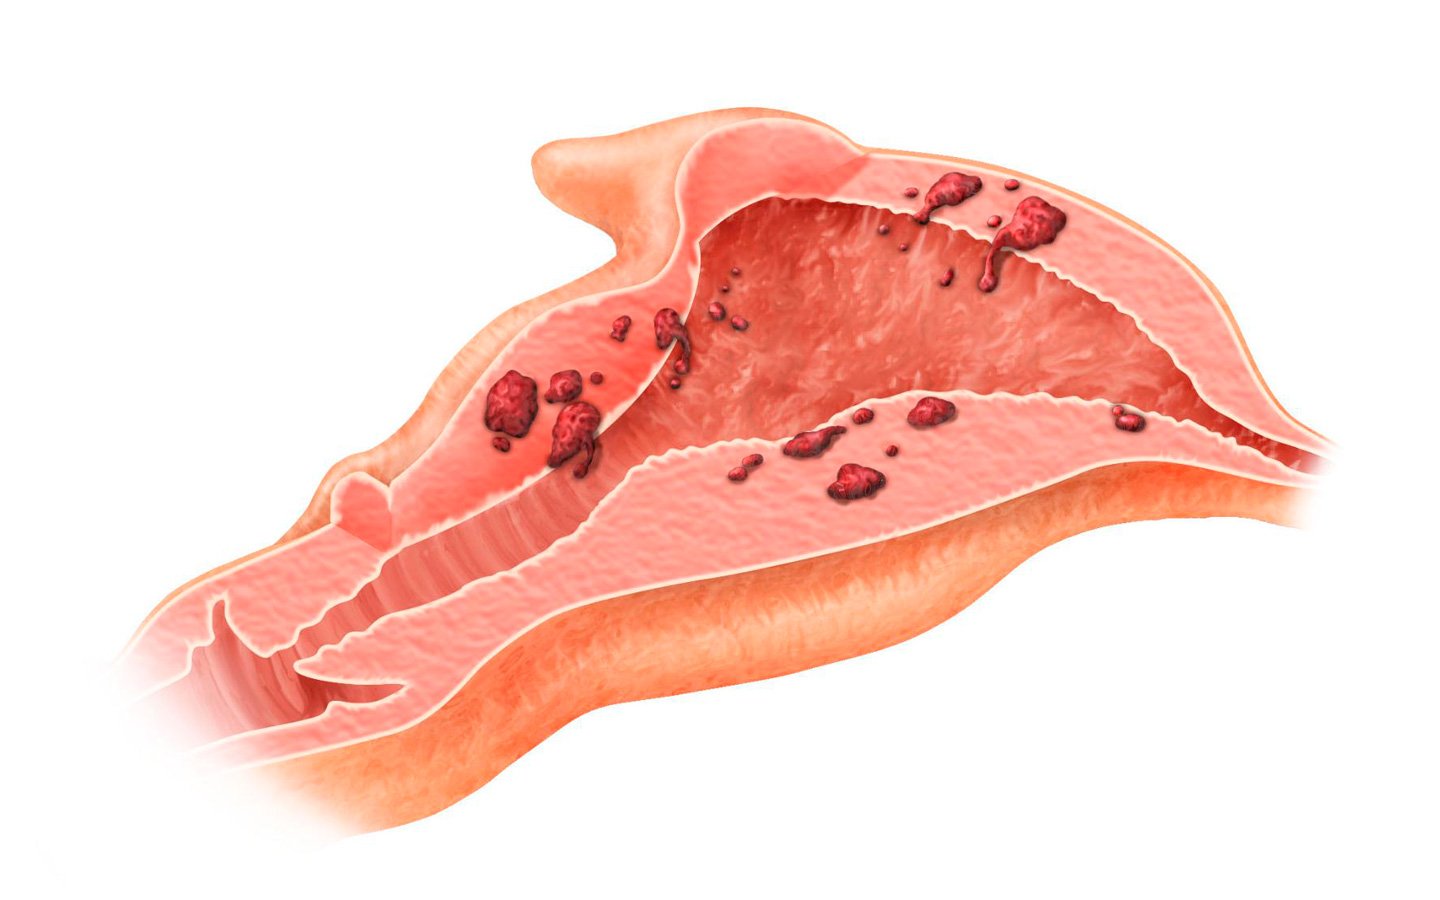

Аденомиоз матки (внутренний эндометриоз) — это гинекологическое заболевание, в основе которого лежит прорастание клеток внутреннего слоя оболочки матки (эндометрия) в мышечный слой (миометрий). Из-за физиологического отторжения вросшего эндометрия перед менструацией и после неё возникают боли и кровянистые выделения, что служит поводом для обращения к доктору. Такая патология распространена у женщин старше 30–40 лет, однако встречаются случаи возникновения недуга и в более раннем возрасте.

При аденомиозе эндометрий прорастает в мышечный слой, формируя островки

- Очаговый. Эндометрий прорастает в мышечную оболочку не по всей матки, имеются лишь поражённые участки в форме небольших островков.

- Диффузный. В этом случае клетки внутреннего слоя матки прорастают по всей поверхности миометрия.

- Узловой или кистозный. При такой форме недуга обнаруживается образование на поверхности мышечной оболочки матки узлов эндометрия, напоминающих опухоли.